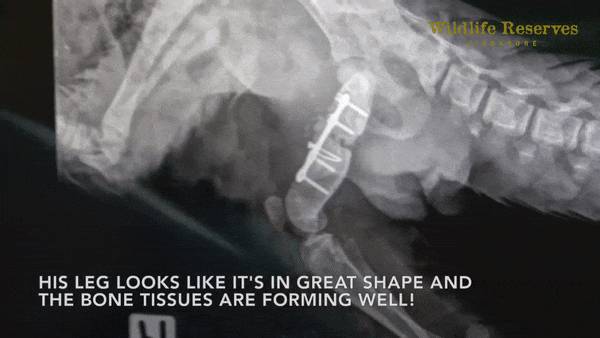

但是医生凭借着高超的技能,从它柔软的大腿内侧动刀,成功为Berani植入了支架,顺利完成了世界上第一例穿山甲手术。

现在可以从X光中清楚看到它恢复得不错